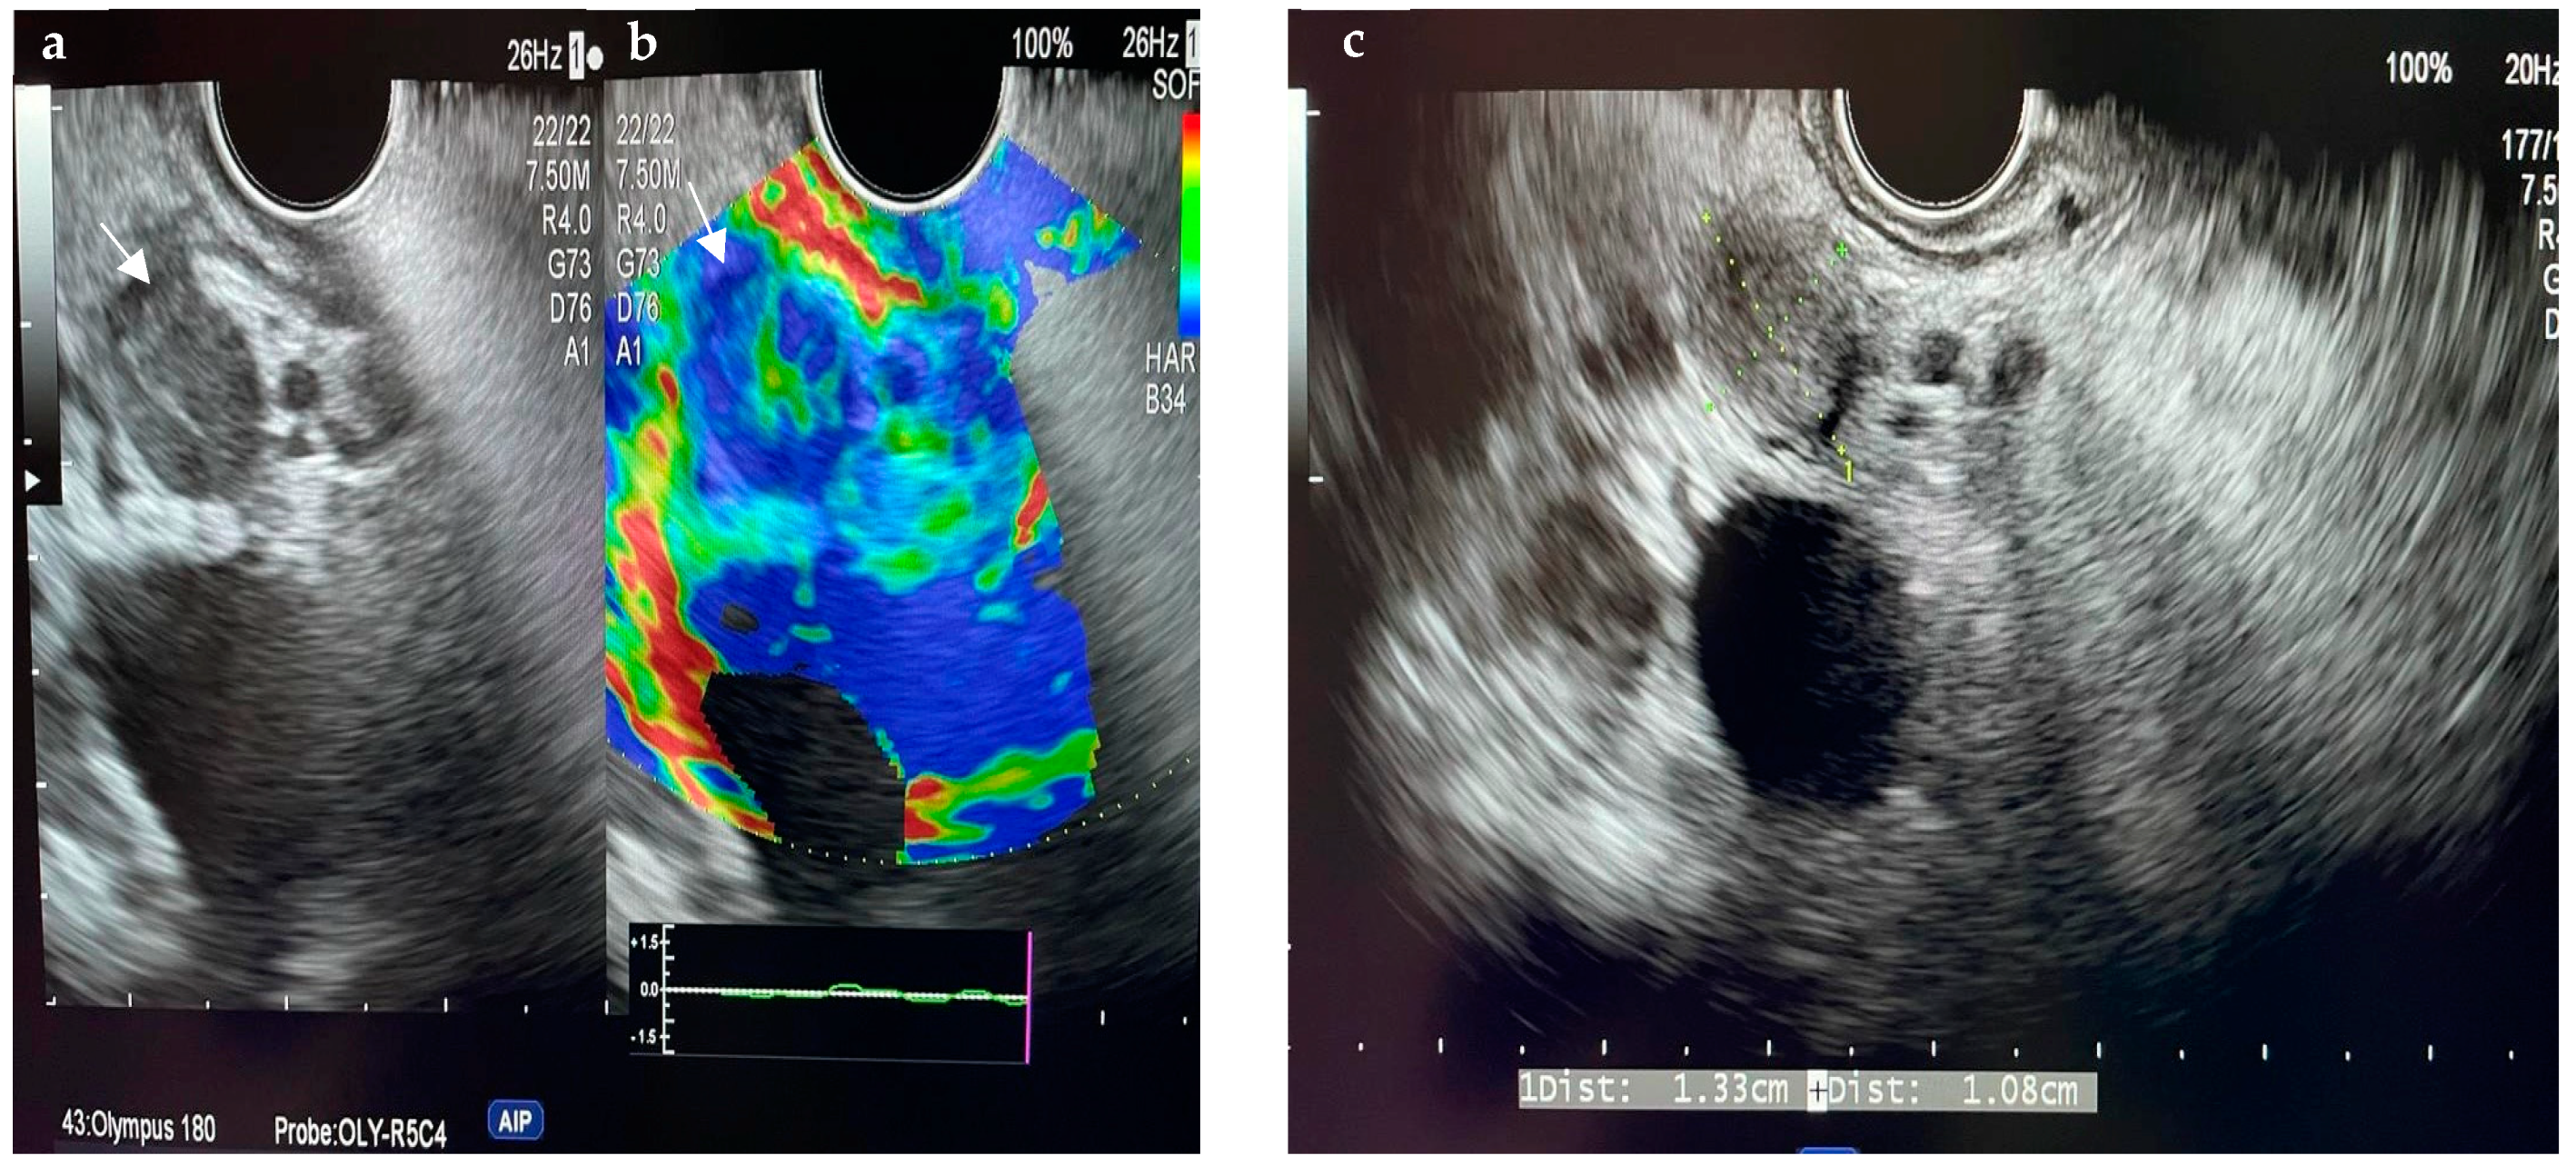

6.4.1. Endoscopic Ultrasound (EUS)

- Orzan, R.I.; Pojoga, C.; Agoston, R.; Seicean, R.; Seicean, A. Endoscopic Ultrasound in the Diagnosis of Extrahepatic Cholangiocarcinoma: What Do We Know in 2023? Diagnostics 2023, 13, 1023. [Google Scholar] [CrossRef] [PubMed]

- Otsuka, Y.; Kamata, K.; Hyodo, T.; Chikugo, T.; Hara, A.; Tanaka, H.; Yoshikawa, T.; Ishikawa, R.; Okamoto, A.; Yamazaki, T.; et al. Utility of contrast-enhanced harmonic endoscopic ultrasonography for T-staging of patients with extrahepatic bile duct cancer. Surg. Endosc. 2022, 36, 3254–3260. [Google Scholar] [CrossRef] [PubMed]